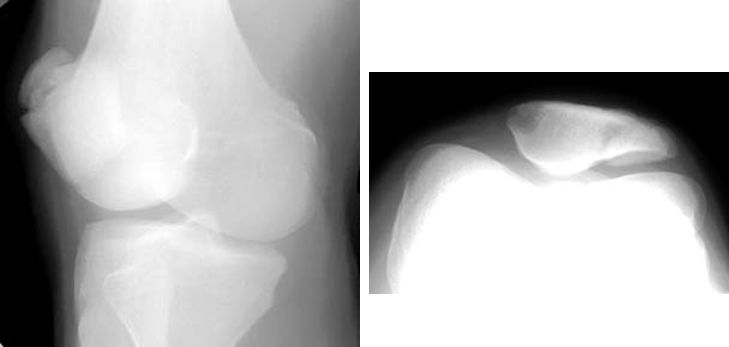

髌骨骨折

疼痛科怎么理疗疼痛科医生、康复理疗科医生、针刀针灸医生应掌握的常见骨科疾病X光片_https://www.jmylbn.com_新闻资讯_第33张

髌骨脱位

疼痛科怎么理疗疼痛科医生、康复理疗科医生、针刀针灸医生应掌握的常见骨科疾病X光片_https://www.jmylbn.com_新闻资讯_第34张